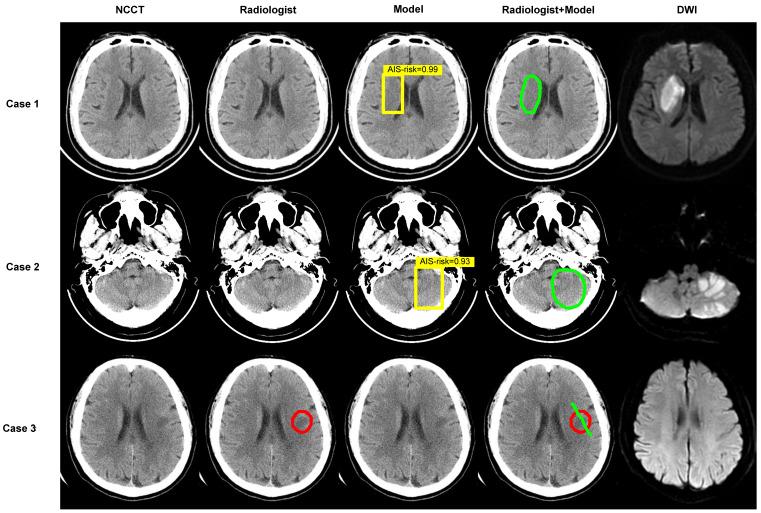

Although non-contrast computed tomography (NCCT) is the recommended examination for the suspected acute ischemic stroke (AIS), it cannot detect significant changes in the early infarction. We aimed to develop a deep-learning model to identify early invisible AIS in NCCT and evaluate its diagnostic performance and capacity for assisting radiologists in decision making. : In this multi-center, multi-manufacturer retrospective study, 1136 patients with suspected AIS but invisible lesions in NCCT were collected from two geographically distant institutions between May 2012 to May 2021. The AIS lesions were confirmed based on the follow-up diffusion-weighted imaging and clinical diagnosis. The deep-learning model was comprised of two deep convolutional neural networks to locate and classify. The performance of the model and radiologists was evaluated by the area under the receiver operator characteristic curve (AUC), sensitivity, specificity, and accuracy values with 95% confidence intervals. Delong's test was used to compare the AUC values, and a chi-squared test was used to evaluate the rate differences. 986 patients (728 AIS, median age, 55 years, interquartile range [IQR]: 47-65 years; 664 males) were assigned to the training and internal validation cohorts. 150 patients (74 AIS, median age, 63 years, IQR: 53-75 years; 100 males) were included as an external validation cohort. The AUCs of the model were 83.61% (sensitivity, 68.99%; specificity, 98.22%; and accuracy, 89.87%) and 76.32% (sensitivity, 62.99%; specificity, 89.65%; and accuracy, 88.61%) for the internal and external validation cohorts based on the slices. The AUC of the model was much higher than that of two experienced radiologists (65.52% and 59.48% in the internal validation cohort; 64.01% and 64.39% in external validation cohort; all < 0.001). The accuracy of two radiologists increased from 62.00% and 58.67% to 92.00% and 84.67% when assisted by the model for patients in the external validation cohort. : This deep-learning model represents a breakthrough in solving the challenge that early invisible AIS lesions cannot be detected by NCCT. The model we developed in this study can screen early AIS and save more time. The radiologists assisted with the model can provide more effective guidance in making patients' treatment plan in clinic.

虽然非对比计算机断层扫描 (NCCT) 是疑似急性缺血性脑卒中 (AIS) 的推荐检查方法,但它不能检测到早期梗死的显著变化。我们旨在开发一种深度学习模型,以识别 NCCT 中的早期隐匿性 AIS,并评估其诊断性能和协助放射科医生决策的能力。:在这项多中心、多制造商的回顾性研究中,从 2012 年 5 月至 2021 年 5 月,从两个地理位置较远的机构共收集了 1136 名疑似 AIS 但 NCCT 未见病灶的患者。根据随访弥散加权成像和临床诊断,确定 AIS 病灶。深度学习模型由两个深度卷积神经网络组成,用于定位和分类。通过受试者工作特征曲线下面积 (AUC)、敏感性、特异性和准确性值及其 95%置信区间评估模型和放射科医生的性能。使用 Delong 检验比较 AUC 值,使用卡方检验评估率差异。986 名患者(728 名 AIS,中位年龄 55 岁,四分位距 [IQR]:47-65 岁;664 名男性)被分配到训练和内部验证队列。150 名患者(74 名 AIS,中位年龄 63 岁,IQR:53-75 岁;100 名男性)被纳入外部验证队列。基于切片,模型的 AUC 分别为 83.61%(敏感性 68.99%;特异性 98.22%;准确性 89.87%)和 76.32%(敏感性 62.99%;特异性 89.65%;准确性 88.61%)在内部和外部验证队列中。模型的 AUC 明显高于两名有经验的放射科医生(内部验证队列中分别为 65.52%和 59.48%;外部验证队列中分别为 64.01%和 64.39%;均<0.001)。当外部验证队列中的患者使用模型辅助时,两名放射科医生的准确率从 62.00%和 58.67%提高到 92.00%和 84.67%。:该深度学习模型代表了在解决 NCCT 无法检测早期隐匿性 AIS 病变的挑战方面的突破。我们在这项研究中开发的模型可以筛选早期 AIS 并节省更多时间。使用模型辅助的放射科医生可以在临床中为患者制定治疗计划提供更有效的指导。